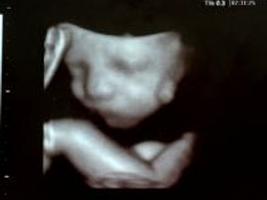

В середине триместра развитие ребенка в утробе матери идет по верному пути. Половые органы сформировались, и вскоре вы сможете увидеть их на УЗИ . У вашего ребенка начали развиваться некоторые основные органы, такие как печень, почки и спинной мозг. Ручки и ножки вашего ребенка могут двигаться, и у него достаточно места, чтобы потянуться, потому что на данный момент его длина составляет всего 3 дюйма.

В конце первого триместра у ребенка полностью формируются пальцы рук и ног, а также глаза, уши, рот и нос.